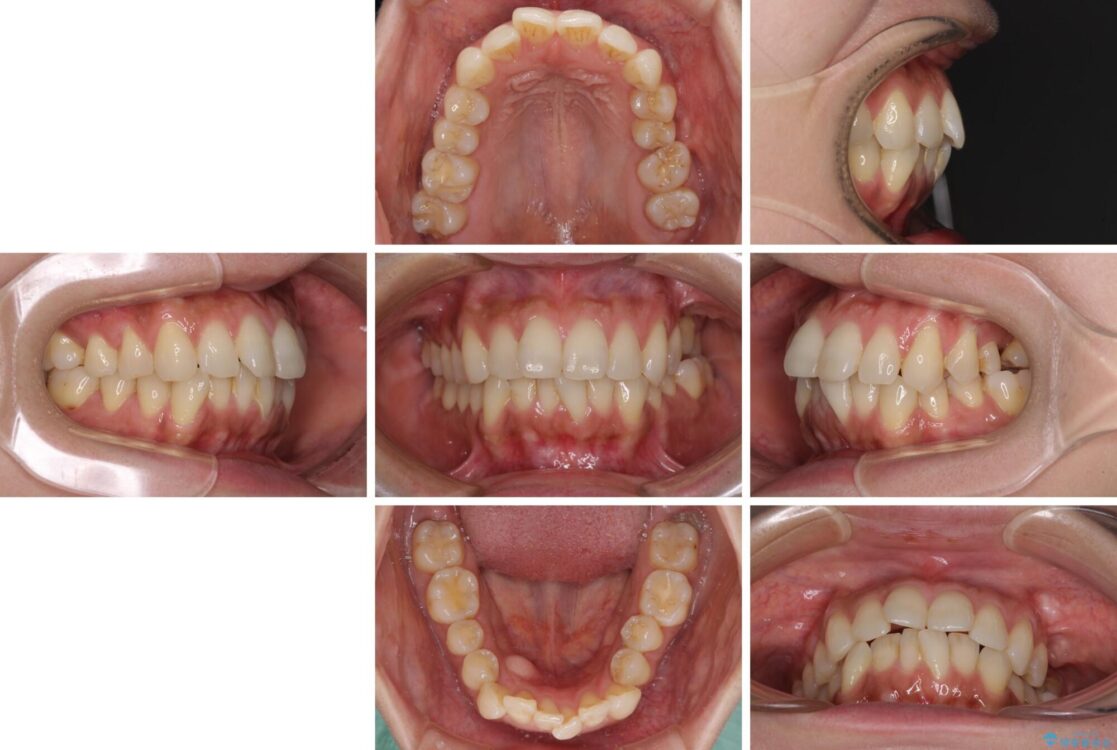

全体的なデコボコと、以前抜歯した歯のスペースを閉じた部分が気になるとのことで来院された患者様です。

左上第一大臼歯を抜歯した際に、スペースを閉じたそうですが、歯が傾斜してものが挟まって不快とのことでした。

治療前

• インビザラインによる矯正治療と奥歯のインプラント治療 治療前画像